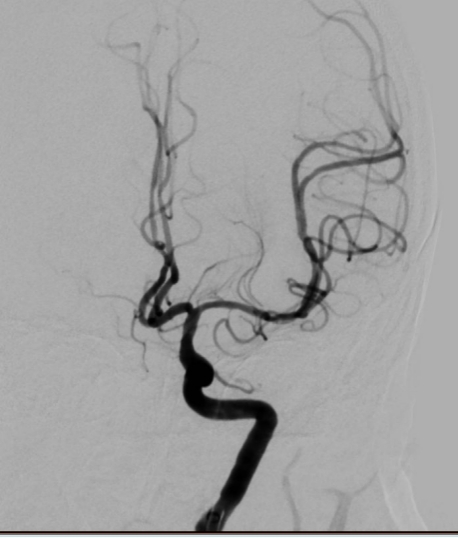

脑血管造影是目前脑血管检查的金标准,是通过动脉插管,使用造影剂显影完成脑血管检查的一种微创方法。其特点:简单、方便、安全、准确、创伤小。我院从2009年开始开展脑血管造影检查,目前开展经桡动脉、股动脉两种路径完成脑血管造影及治疗,桡动脉路径大大减轻患者的痛苦。目前开展的治疗手术:颅内外血管球囊扩张成形术、支架置入术、动脉瘤栓塞术、急症溶栓、取栓术,对于出血性脑血管病患者开展了微创血肿清除术。每年造影检查量约500例左右,治疗量约100例左右。介入技术水平走在了全市前列,取得了广大患者的好评。

图片1.jpg  图片2.jpg

经股动脉入路造影                                                               经桡动脉入路造影